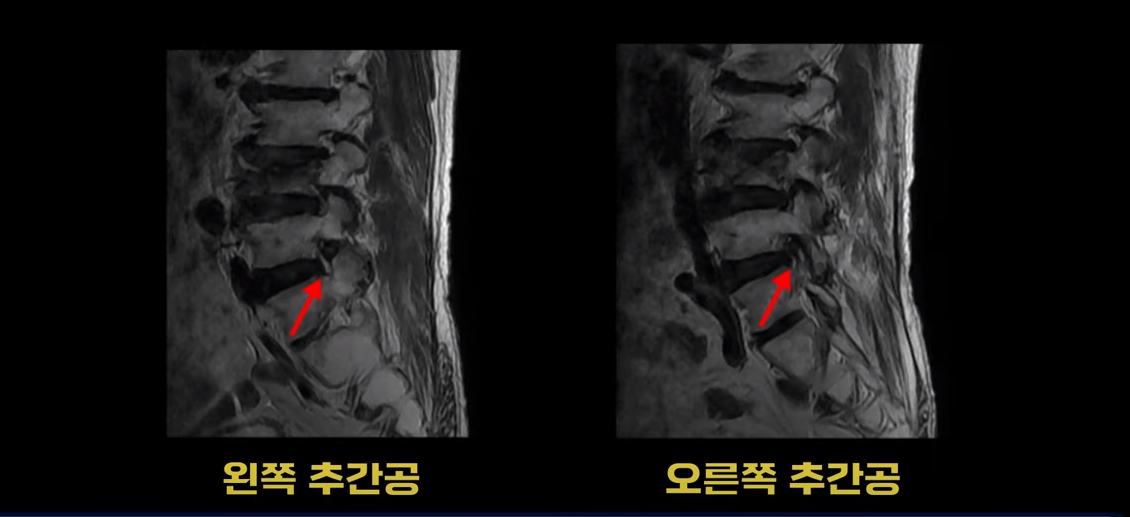

이분 MRI를 보시면 4번 5번과 5번 1번에 협착증수술, 즉 감압술을 한 흔적이 보입니다.

두꺼워진 황색인대를 제거해서 척추관의 공간을 넓힌 것으로 보입니다. 이렇게 수술했어도 신경가지가 척추 좌우로 빠져나가는 추간공은 여전히 노화와 퇴행으로 인해 좁아져 있는 상태입니다.